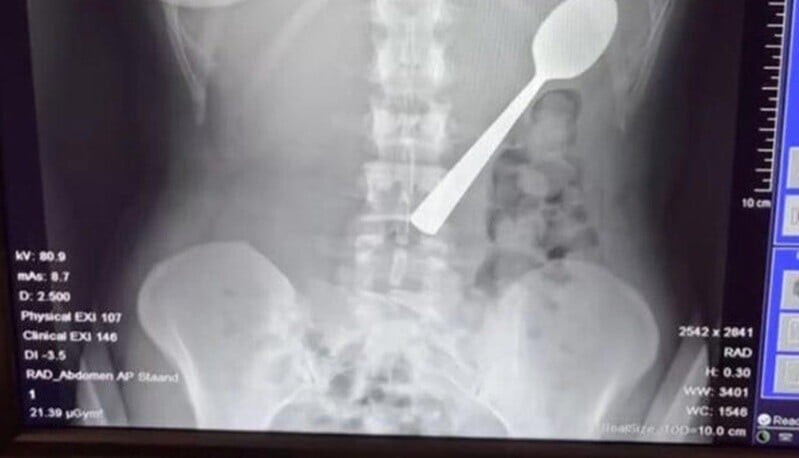

比利時一名女子吃乳酪時,狗狗突然跳到身上,她嚇到吞下17厘米湯匙!(互聯網)

28歲的Reymy Amelinckx向記者展示X光照片,可見一隻湯匙在其體內。她指,當時要用雙手打字發短訊,口含湯匙,就在這時愛犬Marley跳到她身上。她驚慌下頭向後仰,結果湯匙滑進喉嚨,她站起身,十分驚慌。Amelinckx曾試圖用手拿出湯匙但不成功,她只能選擇吞下肚或有機會窒息,最終吞下湯匙。男友放工回家,她因為太尷尬未有告知,又覺得無不舒服,假裝一切正常,未有立即求醫。